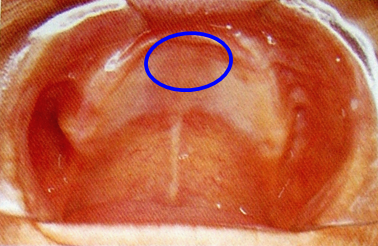

8.腭小凹(palatal fovea)

口内粘液腺导管的开口,位于上腭中缝后部的两侧。

上颌全口义齿的后缘应在腭小凹后2mm处 ,颤动线位于腭小凹的稍前部。

10.颤动线(vibrating line)

位于软腭与硬腭的交界部位。发“啊”音时软腭升高,发音结束后又复归原位,故又称“啊”线。

堵住鼻孔用鼻子出气会使软腭向下降,能明确观察到颤动线。

该线通常作为决定义齿基托后缘的标志,分前、后颤动线,两者之间为后堤区,宽约2~12mm 。